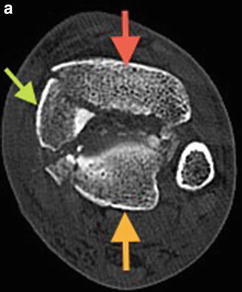

앞쪽의 경우 Chaput, 가쪽(lateral)의 경우 Wagstaffe, 뒤쪽의 경우 Volkmann fragment로 명명하며, medial malleolus가 추가로 있을 수 있습니다.

교정의 순서는 PL, AL, Center, med fragment 순서로 뒤쪽에서 lat 차례대로 진행합니다.